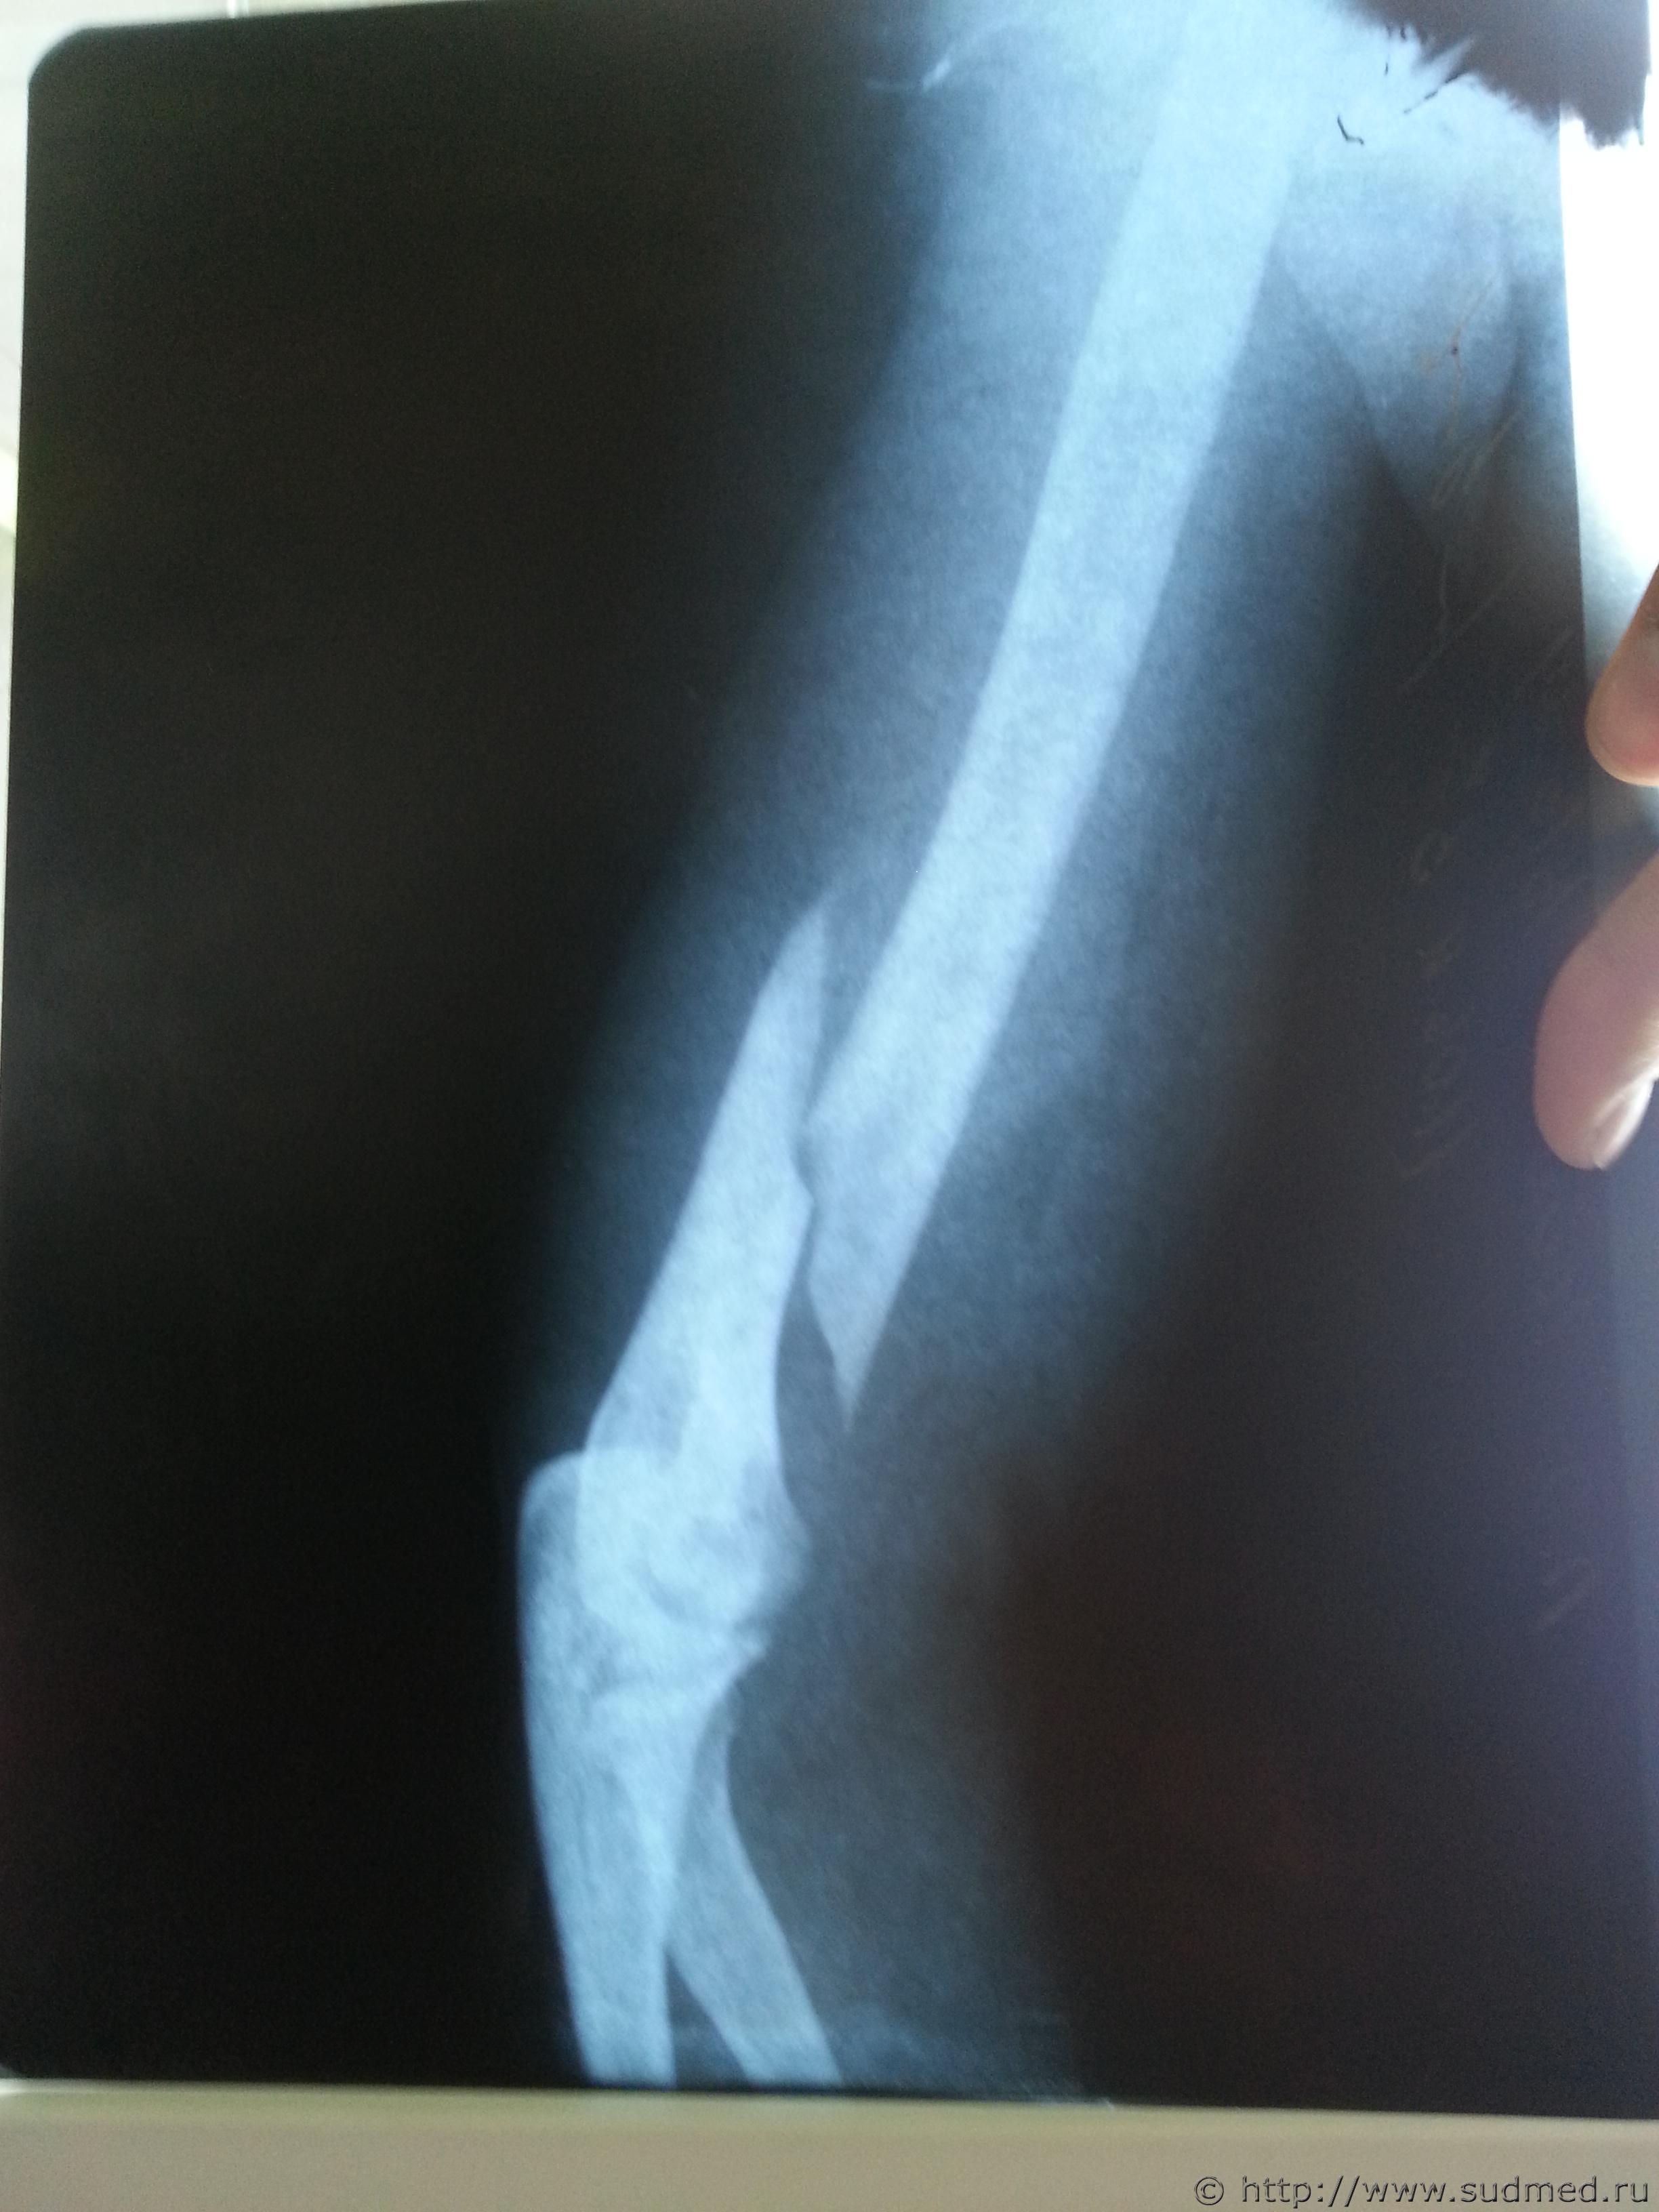

Винтообразный перелом нижней трети части плечеквой кости со смещением отломков, Винтообразный перелом механизм повреждения

Фото перелома до и после операции прилагаю

по первым сканам, что Вы выложили вряд ли можно что-то конкретное сказать, по последнеиу - искючать вариант перелома при обстоятельствах, изложенных в вопросе 1 не стал бы, и еще - место перелома не характерно для возникновения его при падении на вытянутую руку, перелом возможен без наружных повреждений, 4- вопрос не имеет судебно-медицинской составляющей и отношения к экспертам и вообще не знаю кто на такие вопросы может отвечать..кроме шаманов

Согласен с Gladius, место перелома не характерно для падения на руку, а характер перелома по снимкам похож на "винтообразный", по механизму образования как раз типичный для "выкручивания" руки. К сожалению, качество цифровых изображений не позволяет высказаться с уверенностью. Возможно, при изучении оригиналов снимков эксперт сможет сказать больше.